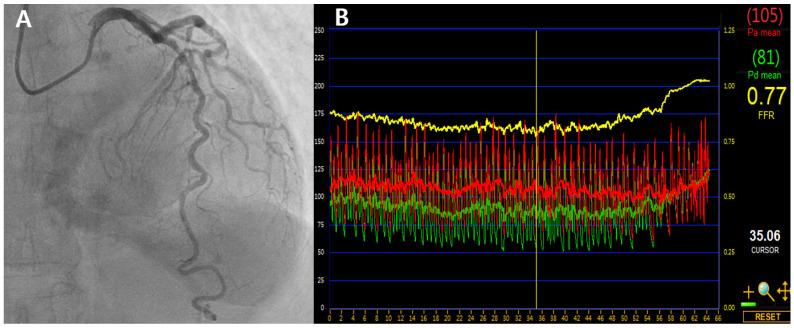

Fractional Flow Reserve in the Left Anterior Descending Artery.

Fractional flow reserve (FFR) is a standard physiological index for guiding coronary revascularization, with a threshold of >0.80 typically used to defer intervention. However, due to its distinct anatomical and physiological features, the left anterior descending artery (LAD) often exhibits lower FFR values than non-LAD vessels for lesions of similar angiographic severity. These vessel-specific differences raise concerns about applying a uniform FFR cutoff across all coronary territories. Observational studies indicate that LAD lesions deferred at an FFR of 0.80 may have similar or better outcomes than non-LAD lesions do. LAD lesions also tend to show lower post-percutaneous coronary intervention FFR values, suggesting that vessel specific target thresholds may be more prognostically appropriate. Additionally, some evidence suggests that instantaneous wave-free ratio may offer greater prognostic value than FFR, specifically in LAD lesions, a trend not consistently seen in other arteries. In patients with acute myocardial infarction and multivessel disease, the prognostic relevance of non-culprit lesion FFR may vary by coronary territory, particularly in the LAD. This review outlines the physiological rationale and clinical evidence for vessel-specific interpretation of FFR, with a focus on the LAD, and explores its potential clinical implications and limitations.